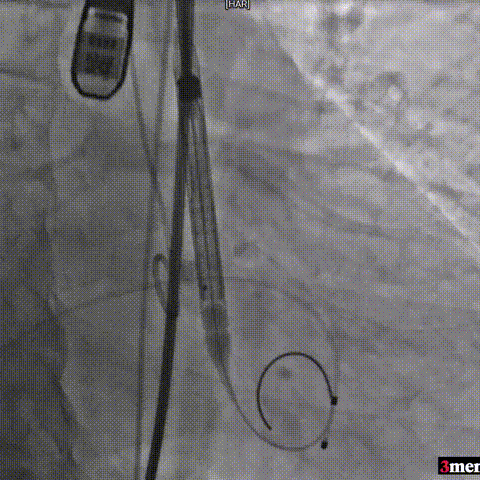

手术过程回顾:

瓣膜定位

瓣膜释放至工作位

瓣膜脱钩

球囊后扩

术后超声提示患者跨瓣压差即刻显著下降,反流量轻微。术中未出现相关并发症,术后患者心功能持续得到改善,效果良好,圆满取得此次手术成功。